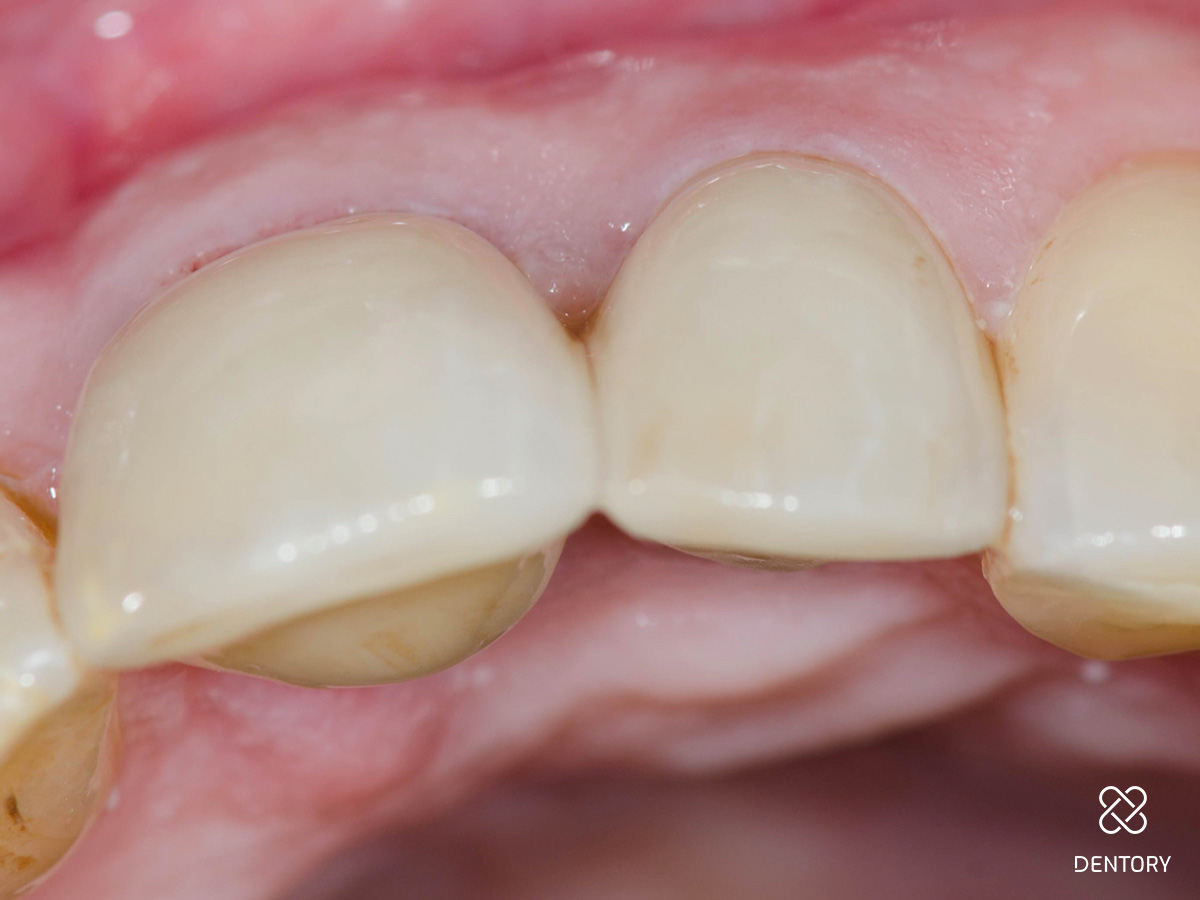

Abbildung 6

Einprobe an 21: Die Einprobe der Krone 21. Die Kronen werden auf Farbe, Form und Passgenauigkeit überprüft.